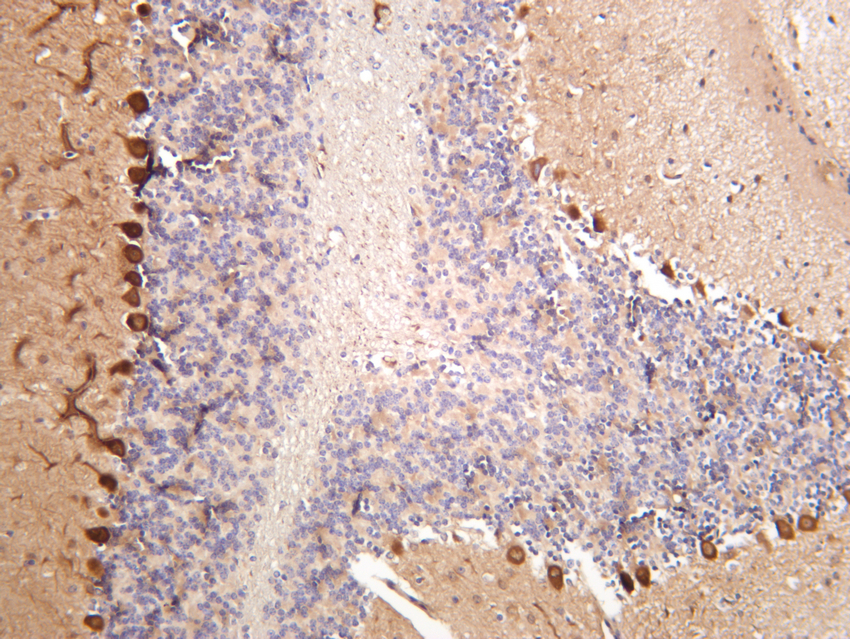

Rusults

circEXOC6B was downregulated in CRC tissues, and its lower expression was associated with poor prognosis of patients. Functional experiments showed that circEXOC6B inhibited growth and increased the 5-fluorouracil-induced apoptosis of CRC cells in vitro and in vivo. Mechanistically, circEXOC6B inhibited the heterodimer formation of RRAGB by binding to it, thereby suppressing the mTORC1 pathway and HIF1A level. In addition, HIF1A upregulated the transcription of RRAGB by binding to its promoter region. Altogether, the results demonstrated that a HIF1A-RRAGB-mTORC1 positive feedback loop drives tumor progression in CRC, which could be interrupted by circEXOC6B.

Conclusions

circEXOC6B inhibits the progression of CRC and enhances the chemosensitivity of CRC cells to 5-fluorouracil by antagonizing the HIF1A-RRAGB-mTORC1 positive feedback loop. circEXOC6B is a possible therapeutic target for CRC treatment.